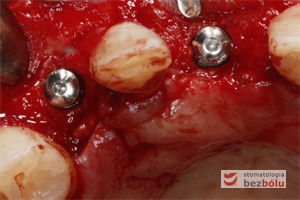

Implanty in situ – widok okluzyjny wprowadzonych wszczepów 1 mm podwyrostkowo

Miniśruby chirurgiczne wprowadzone do implantów – miniśruby zapewniają łatwiejszą identyfikację miejsca wszczepu przy ekspozycji